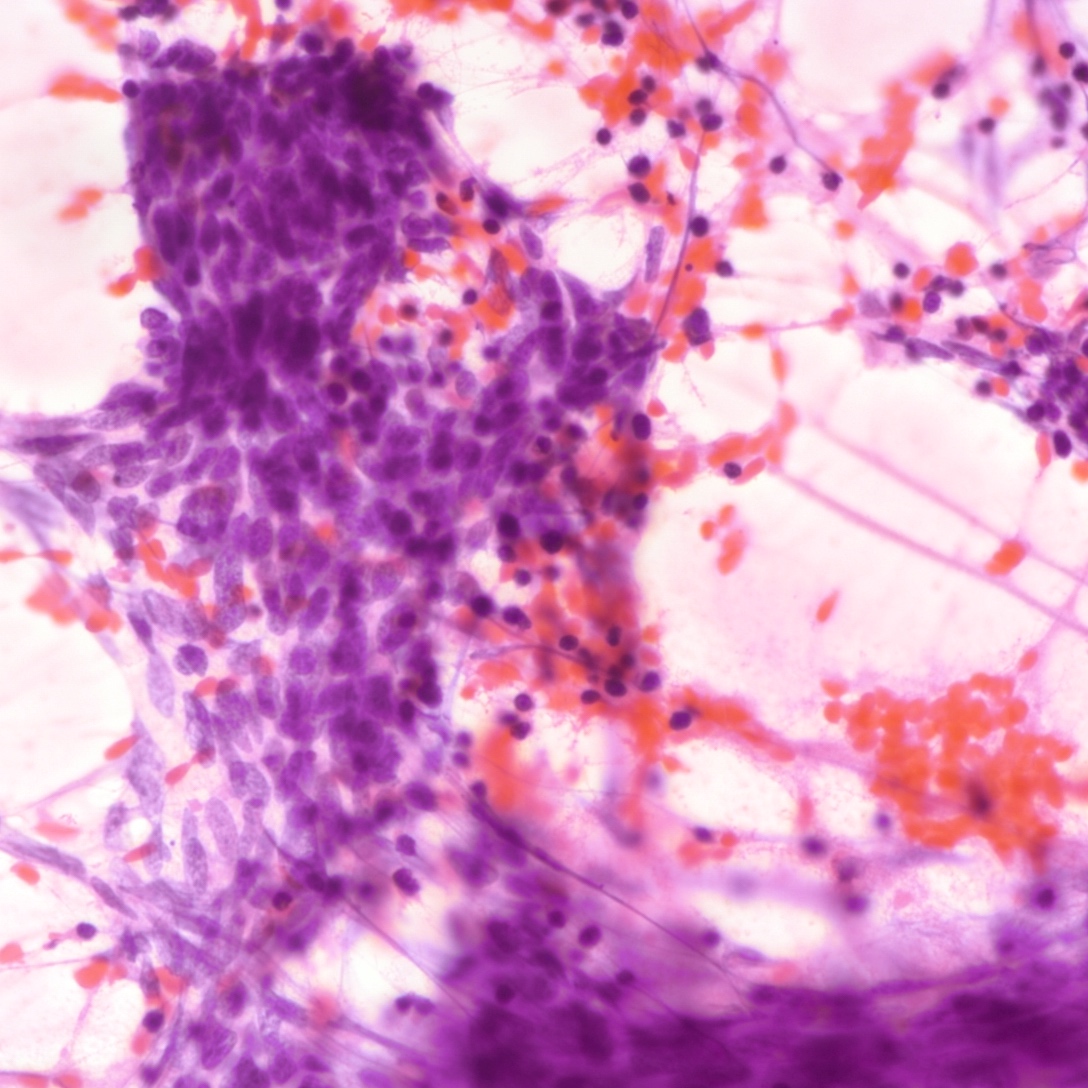

Contributed by Joshua J.X. Li, M.B.Ch.B., Gary M. Tse, M.B.B.S. and Kristen E. Muller D.O.

Small cell carcinoma

Cytology description

- Neuroendocrine features, including nuclear molding and fine salt and pepper chromatin, may be identified in small cell carcinoma

- Necrosis can be present in the background (J Cytol 2011;28:91)

- Smear preparation can accentuate crush artifact

Cytology images